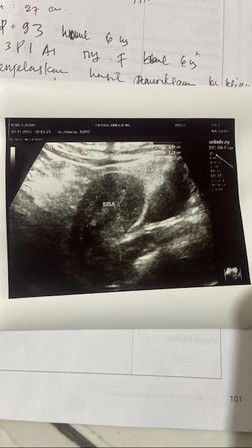

Bun pengen sharing brngkali ada yg sama harus gmna ya .. aku hamil 6w6d td sore pendarahan adalah darahnya se pembalut tnpa sayap yg kecil .. td usg ktnya udah pecah masih ada sisah lebih dri 3centi hrus dikuret cuma aku kurang yakin soalnya ga usg tranvaginal .. apa aku harus nunggu dlu ya seminggu lg buat usg🥹 masih berharap klao janinnya masih ada mungkin cuma kecapean aja .. ini hamil ke 3 yg pertama keguguran yg ketiga juga masa harus keguguran lg 🥹

Baca lagiasalamualaikum bun, usia ke hamilan saya dari hpht 7minggu 2 hari, tapi kemarin usg baru 6 minggu 4 hari, saya keluar plek bercak tampa gumpalan langsung ke dokter kandungan di periksa lewat transvaginal, alhamdulillah embrionya sudah didalam rahim dan alhamdulillah udah ada detak jantungnya, tapi masih ada darah netes ke cd, apa itu aman bun buat kehamilan saya? kemarin pas usg di kasih obat penguat sama dokternya, doain ya bun kehamilan ku sehat selalu 🤲

Baca lagisya juga sama bun usia 5week tp udah 4 hari flek coklat gitu terus kemaren periksa ke dokter dan usg..tp usg yg d perut gk keliatan akhirnya pake yg tranvaginal alhamdulillah keliatan walau kecil katanya gk sesuai sama hpl nya..d kasih vitamin sama obat penguat kandungan tp sekarang malah darah segar yg keluar nya bun tp gk bnyak..siapa tau ad y g bisa kasih solusi krna emang kami sudah kepengen bnget punya anak lg jadi ini bikin stres d saya nya 🙏🙏

Baca lagiSaya kemarin seperti itu bun, hamil jalan 12 week. Pertama flek coklat tapi tidak banyak, akhirnya langsung ke RSIA dan dilakukan usg transvaginal karena lebih akurat bun alat yg dimasukan ke dalam vagina setelah di cabut akan terlihat volume flek kita yg menempel pada alat tersebut. Dokter juga bilang bahwa janin saya sehat namun saya harus rawat inap karena harus penanganan cepat. Dokter bilang gejala BO. Tapi alhamdulillah janinnya bisa ke tolong.